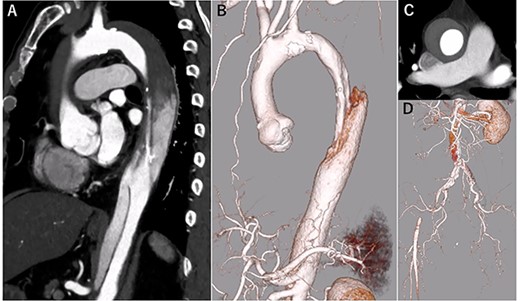

A 68-year-old man developed severe acute back pain and was diagnosed with acute type A aortic dissection with enhanced computed tomography (eCT) in the emergency department of our institute (Fig. 1A and B). The false lumen of the arch and ascending aorta was thrombosed (the maximum short diameter of the ascending aorta was 43.3 mm, the maximum diameter of the false lumen at the ascending aorta was 17.7 mm, Fig. 1C), and the primary entry was placed at the descending aorta. In addition, malperfusions were observed in the right renal artery and both iliac arteries (Fig. 1D). Therefore, we decided to perform TEVAR with the petticoat technique because of the rapid increase in true lumen blood flow.

eCT at diagnosis. (A): Sagittal view, (B) 3D reconstruction of the ascending and descending aorta, (C): Axial view of the ascending aorta and (D): 3D reconstruction of the abdominal aorta and iliac artery.